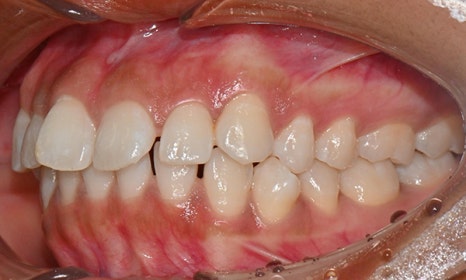

위아래 앞니 사이가 벌어져서 공간이 있었고, 앞니에 약간씩 배열이 틀어진 덧니가 있었습니다. 정면에서 보았을 때 윗니와 아래 앞니가 깊게 물려서 아래 앞니가 잘 보이지 않는 과개교합 양상을 보이고 있었습니다. 또한 왼쪽 아래 작은 어금니가 90도 앞으로 돌아가서 좌측 치아 배열 및 교합이 좋지 않은 상태였습니다.

초진시 구내사진 (2025. 3.31)

교정 마무리 후 사진으로 위아래 치아 배열이 개선되었고 공간이 모두 닫혔습니다. 위아래 앞니가 깊게 물리는 과개교합도 처음에 비하여 많이 개선되었습니다. 다만 아래 작은 어금니 배열로 인하여 왼쪽 어금니 교합은 아직 완벽하지 않은 상태로, 추후 본국으로 돌아가서 자료를 transfer 해드려서 이어서 치료를 받기로 하셨습니다.